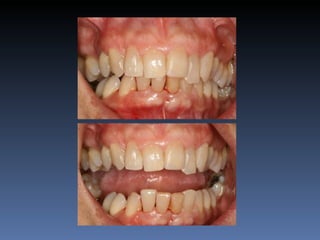

BOX 1

Maura Graça Montereiro

Idade – 59 anos

Sexo – Feminino

Raça – Caucasiana

ASA – II

Data- 27-04-2012

Diagnóstico: Desdentada total maxila

já reabilitada com “All-on-four” híbrido;

periimplantite dos implantes anteriores.

Plano de tratamento:         Remoção dos implantes

anteriores, instalação de dois implantes Zigomáticos

e dois implantes posteriores na tuberosidade.